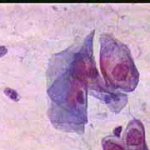

Papanicolaou: Πλακώδη επιθηλιακά κύτταρα κυρίως της επιφανειακήςστιβάδας, περίπου κατά50% και πλέον οξεόφιλα (16η ημέρα κύκλου!) . Ωστόσσο και αρκετά της διαμέσου και της παραβασικής, εν μέρει με διογκωμένους, ανισομεγέθειςαρραιοχρωματικούςδιαυγείςπυρήνεςKοιλοκυττάρωση.Η εικόνα συνηγορεί για δυσπλασία σοβαρού βαθμού.

Λόγω και του κολποσκοπικούευρήματος, μικροβιοψία που κατεδειξε ιστολογικώς CIN III